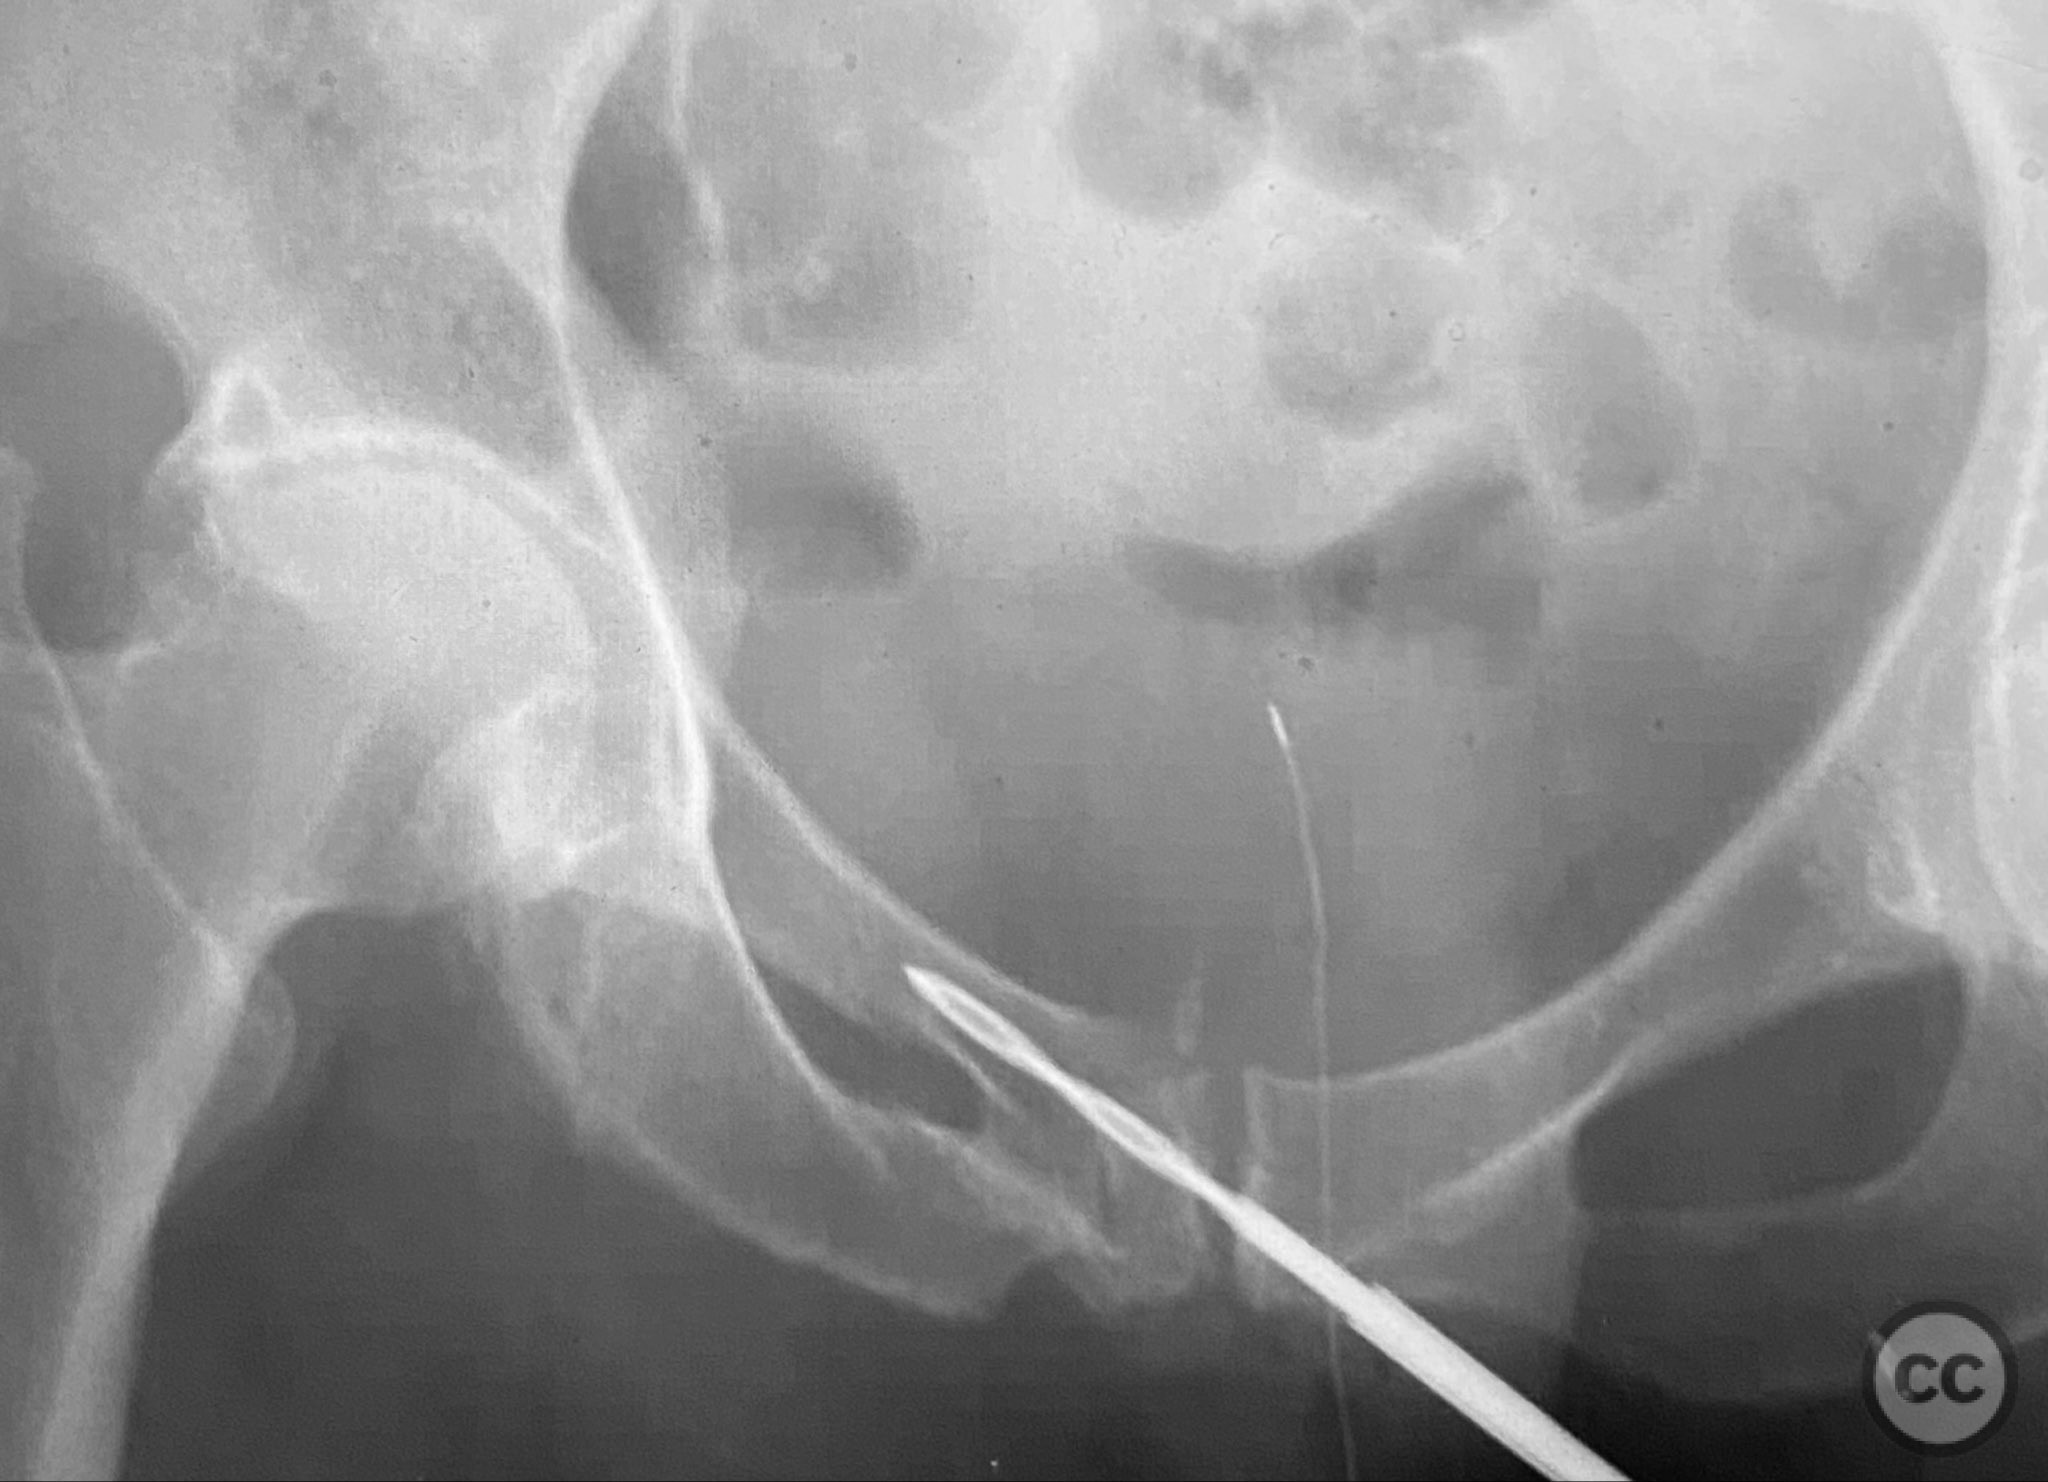

Intraoperatively, a 3.5mm drill was used through a protective sleeve to initiate the screw pathway across the superior pubic ramus. Due to poor bone quality, a 2.5mm drill was subsequently employed; however, resistance was encountered as the drill tip engaged the dense cortical apex of the anterior acetabular wall. The drill became lodged in this region. To avoid drill breakage, manual extraction using pliers was considered; however, the surgeon elected to carefully deflect and advance the drill manually, successfully completing the pathway. Screw length was measured directly from the embedded drill tip. A 4.5mm cortical screw was then inserted trans-symphyseally along the prepared medullary canal, achieving stabilization of the unstable ramus fracture. Postoperative CT confirmed appropriate screw trajectory and demonstrated the dense cortical bone at the anterior acetabular wall where the drill tip had engaged.

Orthopaedic implants used:   4.5mm cortical screw